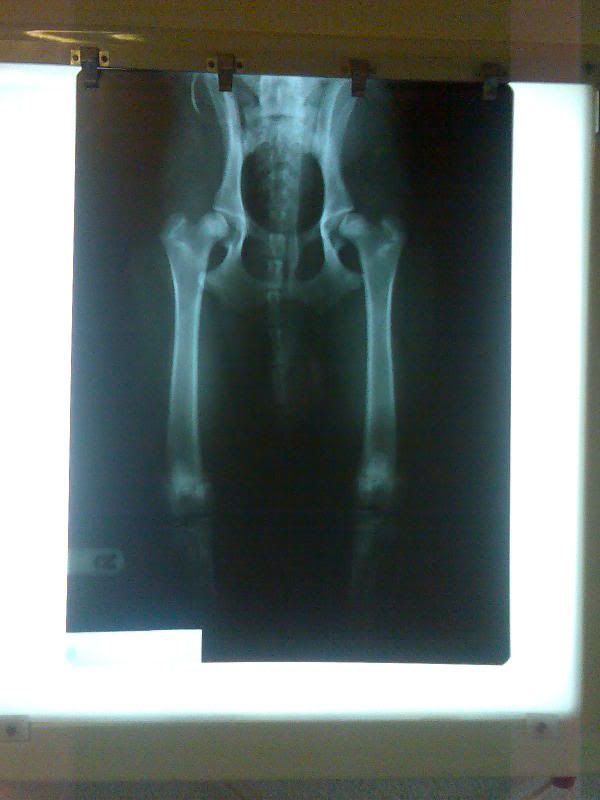

Wat ik overigens "helemaal" niet snap is, dat u eerder deze week een vreselijke uitslag heeft gekregen en dat Zonda waarschijnlijk HD-E heeft en een bekkenkanteling moet ondergaan